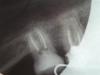

*Lena Опубликовано 3 января, 2010 Поделиться Опубликовано 3 января, 2010 Уважаемые форумчане С Новым годом!!!! А теперь вопрос: Нижняя восьмерка справа 7 месяцев назад удалили нервы в каналах и запломбировали гутаперчей. Боль при накусывании так и не прошла, вернее верхней пары у него нет, реагировал, когда я его задевала щеткой или пальцем. Вот пошла перелечивать по гарантии а врач говорит что нужно удалять, так как каналы до конца запломбировать не возможно (сильное сужение и инструмент не проходит). И действительно, я ощущала как она стучит в нем "иголочкой" и дальше она не идет. Каналы все таки распломбировала, положила лекарство на неделю, сейчас реакция зуба на надавливание и прикосновение прошла. Может все таки попробовать запломбировать его еще раз? И чем? Я так думаю что гутаперчей бесплатно (по гарантии) перепломбировывать больше не будут, предложат какую нибудь лечебную пасту по дешевле. Снимок прилагаю, это после 7 месяцев лечения, перед распломбировокй. Зуб стоит на месте 7 , так как в детстве удалили 6 и все остальные сдвинулись, удалять его очень не хочется! Ссылка на комментарий

zybnaya feya Опубликовано 3 января, 2010 Поделиться Опубликовано 3 января, 2010 Так в том то и дело, что доктор говорит до верхушки запломбировать не возможно, так как канал сузился и не проходим, что это моя физиологическая особенность, вот так вот, и пока лечила, все время говорила что зря взялась его перелечивать по гарантии, так как на воспаление гарантия не распостроняется, (какое воспаление я не поняла), и что она не виновата в том, что у меня не проходимые каналы, а когда я ее поправила, что это у меня не 7 а 8 зуб и рассказала про удаление 6 в детстве, она сказала что восьмерки вообще лечению не подлежат, а только удалению!!! Вот я и не знаю что делать дальше, а зуб то жалко, тем более он стоит на месте 7 и редко кто из врачей видит что это 8.Спасибо вам огромное за ответ! И С НОВЫМ ГОДОМ!Какая разница 7 или 8? Есть проблема и ее надо решать.То что корень сужаеться к верхушке,так это не ваша особенность,а анатомическая особенность любого корня. По снимку у вас нормальные каналы ,проствет виден до верхушки. Ищите другого доктора-нет непроходимых каналов-есть кривые руки и несостоятельность обеспечения и образования доктора. Ищите того ,кто работает машинной эндодонтией с обязательным использованием коффердама.Зуб МОЖНО пролечить эндодонтически,потом вкв +коронка(там у вас еще кроме кариеса корней 8 и 7 отвратительное эндо в 7)Их оба перелечивать Ссылка на комментарий

*Lena Опубликовано 3 января, 2010 Автор Поделиться Опубликовано 3 января, 2010 (там у вас еще кроме кариеса корней 8 и 7 отвратительное эндо в 7)Их оба перелечиватьИзвините, не поняла про кариес корней в 8? то, что 7 нужно перелечивать, я догадываюсь, лечен был очень давно, но что в 8 кариес? Я думала мне его пролечили нормально 7 месяцев назад..., а болел при надавливании из-за недопломбировки каналов (невозможности-как врач сказала). Поясните пожалуйста как выглядит кариес в 8 на снимке? Что бы я могла разговаривать со своим доктором ну и показать на снимке при необходимости. Да, еще только сейчас поняла что мой снимок вверх ногами, ну тоесть зубами получился, зуб 8 нижний правый (с моей стороны правый) его хорошо видно, а обрезаный это 7. Ссылка на комментарий

zybnaya feya Опубликовано 3 января, 2010 Поделиться Опубликовано 3 января, 2010 Извините, не поняла про кариес корней в 8? то, что 7 нужно перелечивать, я догадываюсь, лечен был очень давно, но что в 8 кариес? Я думала мне его пролечили нормально 7 месяцев назад..., а болел при надавливании из-за недопломбировки каналов (невозможности-как врач сказала). Поясните пожалуйста как выглядит кариес в 8 на снимке? Что бы я могла разговаривать со своим доктором ну и показать на снимке при необходимости. Да, еще только сейчас поняла что мой снимок вверх ногами, ну тоесть зубами получился, зуб 8 нижний правый (с моей стороны правый) его хорошо видно, а обрезаный это 7. http://s03.radikal.ru/i176/1001/e3/41bf014dd2bb.jpgДа понятно ,что перевернут снимок,не переживайте. на снимке отметила гле находяться верхушки корней и вы можете видеть расстояние недопломбированных каналов.Пока оно будет-будут боли при надавливании и приеме жесткой пищи.Т.к. эти места инфицированы и служат очагом хронического воспаления. Кариес корня имееться под пломбами и в 8 и в 7 зубе Ссылка на комментарий

Бело4ка Опубликовано 3 января, 2010 Поделиться Опубликовано 3 января, 2010 http://s03.radikal.ru/i176/1001/e3/41bf014dd2bb.jpgДа понятно ,что перевернут снимок,не переживайте. на снимке отметила гле находяться верхушки корней и вы можете видеть расстояние недопломбированных каналов.Пока оно будет-будут боли при надавливании и приеме жесткой пищи.Т.к. эти места инфицированы и служат очагом хронического воспаления. Кариес корня имееться под пломбами и в 8 и в 7 зубеИ похоже, что фрагмент инструмента в медиальном канале 8 есть. Ссылка на комментарий

zybnaya feya Опубликовано 3 января, 2010 Поделиться Опубликовано 3 января, 2010 И похоже, что фрагмент инструмента в медиальном канале 8 есть.Да,очень нохоже. Возможно это и есть причиа "непроходимости" Ссылка на комментарий

Ion Опубликовано 3 января, 2010 Поделиться Опубликовано 3 января, 2010 Там, в том зубе 100% -ый оствлен инструмент , при увеличении снимка, и его видно. Обьязательно надо, тот канал перелечить !!! Ссылка на комментарий

*Lena Опубликовано 4 января, 2010 Автор Поделиться Опубликовано 4 января, 2010 Уф... немного остыла, подумала и еще раз зашла сюда за советом. А можно на моем снимке показать где (в каком месте) оставлен инструмент? Есть ли перспектива у зуба "прожить" в таком состоянии? Хоть у него и нет пары вверху ? (7 и 8 удалены, 6 еле живая...) но ведь в планах протезирование, кушать то чем то нужно, хотелось бы снизу избежать проблем со съемным протезом или может быть имплантантами. (будет зависеть от финансов). И еще прикладываю "контрольный" снимок 7 месячной давности перед пломбировкой каналов, в зубе "иголочки" не этот ли инструмент там остался? И если можно, поясните полностью не грамотному человеку в стоматологии что такое медиальный канал? это справа или слева на снимке если я на него смотрю? Тут в мониторе компа? уж и не знаю как правильнее свою мысль выразить, извините за каламбур. Ссылка на комментарий

Бело4ка Опубликовано 4 января, 2010 Поделиться Опубликовано 4 января, 2010 Уф... немного остыла, подумала и еще раз зашла сюда за советом. А можно на моем снимке показать где (в каком месте) оставлен инструмент? Есть ли перспектива у зуба "прожить" в таком состоянии? Хоть у него и нет пары вверху ? (7 и 8 удалены, 6 еле живая...) но ведь в планах протезирование, кушать то чем то нужно, хотелось бы снизу избежать проблем со съемным протезом или может быть имплантантами. (будет зависеть от финансов). И еще прикладываю "контрольный" снимок 7 месячной давности перед пломбировкой каналов, в зубе "иголочки" не этот ли инструмент там остался? И если можно, поясните полностью не грамотному человеку в стоматологии что такое медиальный канал? это справа или слева на снимке если я на него смотрю? Тут в мониторе компа? уж и не знаю как правильнее свою мысль выразить, извините за каламбур. Медиальный корень - это тот, который ближе к 5. В нём 2 канала. В одном из них вероятно есть отломок инструмента. На снимке с иглами его или ещё нет, или игла прям до него доходит, но 100% утверждать не берусь. А вот на снимке, где иголок нет, очень похоже. Эндодонтические инструменты ломаются в процессе работы и у опытных врачей. За это доктору голову рубить не стоит. Просто теперь нужно искать другой путь выхода из сложившейся ситуации. Каждый доктор выберет свой в соответствии со своими знаниями и умениями. Медиальный корень - это тот, который ближе к 5. Ну или к 7. А на мониторе - левый. Ссылка на комментарий

zybnaya feya Опубликовано 4 января, 2010 Поделиться Опубликовано 4 января, 2010 (изменено) Уф... немного остыла, подумала и еще раз зашла сюда за советом. А можно на моем снимке показать где (в каком месте) оставлен инструмент? Есть ли перспектива у зуба "прожить" в таком состоянии? Хоть у него и нет пары вверху ? (7 и 8 удалены, 6 еле живая...) но ведь в планах протезирование, кушать то чем то нужно, хотелось бы снизу избежать проблем со съемным протезом или может быть имплантантами. (будет зависеть от финансов). И еще прикладываю "контрольный" снимок 7 месячной давности перед пломбировкой каналов, в зубе "иголочки" не этот ли инструмент там остался? И если можно, поясните полностью не грамотному человеку в стоматологии что такое медиальный канал? это справа или слева на снимке если я на него смотрю? Тут в мониторе компа? уж и не знаю как правильнее свою мысль выразить, извините за каламбур. *Lena' ,простите за прямоту,но скажу. Доктор который измеряет длину иглами Миллера(это ТАКОЙ совок) не пользуясь апекслокатором и коффердамом,я про мед обработку уже могу докадываться-добра вашим зубам не сделает и тем более не исправит данную ситуацию. У нее просто нет на это подходящего оборудования. Обломанный инструмент не приговор. Сложно его конечно вытащить или в лучшем случае обойти,но можно. НО! Для этого нужен ультразвуковой наконечник с специальными насадками и машинная эндодонтия. Повторюсь-ищите доктора с нормальным оснащением и знаниями. Изменено 4 января, 2010 пользователем zybnaya feya Ссылка на комментарий